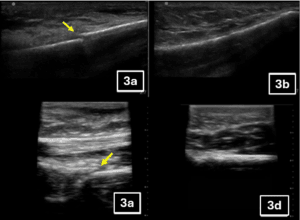

Abdominal Right Upper Quadrant View. The RUQ view characteristics that were evaluated included the difference in echogenicity of the renal cortex and liver, clarity of blood vessels in the liver parenchyma, distinction of the medullary pyramids in the renal cortex, far-field resolution, and color flow Doppler of vessels in the renal pelvis (Figure 3; Appendix 5, Supplemental Table 1). For image quality, the handhelds with the highest image quality scores were the Mindray® (12.00), KosmosTM (11.38), Vscan AirTM (11.38), and Clarius® (11.25) — without a statistically significant difference between the devices. In comparison, LumifyTM and Butterfly iQ+TM had statistically lower total image quality scores. When ranked against each other, KosmosTM, Mindray®, and Vscan AirTM were rated as the top three by most experts.

Figure 3A. Abdominal Right Upper Quadrant Views acquired from the same pediatric model using six handheld ultrasound devices: (A) Butterfly iQ+™, (B) Clarius®, (C) Kosmos™, (D) Lumify™, (E) Mindray®, and (F) Vscan Air™.

Cardiac Apical 4-chamber View. The apical 4-chamber view characteristics that were evaluated included endocardial definition, clarity of valve leaflets, clarity of the lateral tricuspid valve annulus, far-field resolution, and color flow Doppler of the left ventricular outflow tract and mitral valve (Figure 3; Appendix 5, Supplemental Table 2). For image quality, the handhelds with the highest image quality scores were the KosmosTM (12.50), Vscan AirTM (12.38), Mindray® (11.75), Clarius® (10.38), and LumifyTM (10.38) — without a statistically significant difference between the devices. When ranked against each other, the devices finished in the same order. Butterfly iQ+TM was statistically inferior to other devices by total image quality score (6.00) and ranking score (11).

Superficial Neck and Lung Views. The superficial neck and lung view characteristics that were evaluated included the clarity of the carotid artery/internal jugular vein, color flow Doppler of carotid artery/internal jugular vein, difference in echogenicity of the thyroid gland, contrast of chest wall vs. pleural line, and clarity of lung sliding (Figure 3; Appendix 5, Supplemental Table 3). For image quality, the handhelds with the highest image quality scores were the Vscan AirTM (13.00), Clarius® (12.38), and KosmosTM (12.13) — without a statistically significant difference between the devices. LumifyTM and the Butterfly iQ+TM were inferior for image quality of superficial structures. When ranked against each other, Vscan AirTM (39) ranked highest, followed by KosmosTM (36) and Clarius® (33). Mindray® did not have a linear transducer and was excluded from the evaluation of superficial neck and lung views.